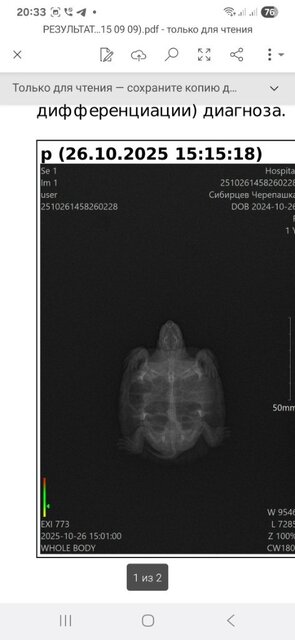

Тульская область.Тула , имя Евгений , мой возраст 42...владею недавно(3недели)красноухой черепашкой...ей уже год и 2 месяца, её вес был 52грамма , сейчас 46 грамм...попала ко мне с опухшими глазами и ничего не ела, глаза пролечили, открыла глаза и сразу налупилась 3 улитки, ракушки я не стал скармливать, тоьько тельце улиток, гусеницы шт. 2 , гамаруса...на следующий день сьела кусок щуки....теперь у нее темпия ...вздутие , плавает на поверхности и не может нырнуть....год черерашка жила в 50 литровке , воды примерно 15 литров, сейчас переселил в 200литровку , воды оде то 90 литров...камни лава под выход на обогрев , в террариум замущены улитки и надводные растения пистич и ряска....освещается камень лампой 2в1 с озона....скоро пииедет уф лампа...встановлен внутренний фильтр , обогреватель, старый не раблтал долго ,видимо,....спираль нерегорела когда то....что настораживает, так это то, что черепаха ничего не ест и теряет в весе...сейчас 46 грамм , было 52....прилогаю фото гентгена и фото нового места обитания

Этот рентген делали в ветклинике не профильного направления.